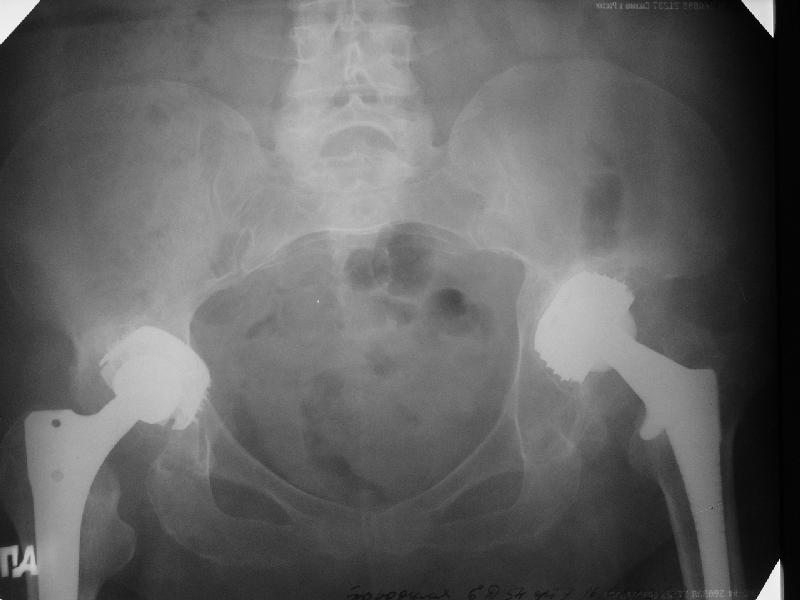

В наше отделение обратилась больная (родственница одного из сотрудников) 1948 г.р. В 2002 г. тотальное эндопротезирование тазобедренных суставов в Кургане.

Август 2002 г.

24 апреля 2005 г. левый сустав фас

С выбором имплантата можно не согласиться, но скорее всего просто поставили то, что было в наличии. :( Вертлужный компонент установлен

слишком медиально. По представленным рентгенограммам нельзя исключить нарушение целостности дна вертлужной впадины. Даже если в данным момент нестабильности нет, то она обязательно возникнет и скорее всего, создаст

На представленных Р-граммах явных признаков нестабильности эндопротеза нет. Чашка хоть и медиализирована, но стоит так же, как и 3 года назад и остеолиза нет. Есть остеолиз вокруг проксималного отдела ножки, но линия тонкая и не захватывает дистальный отдел. Судя по клинике, можно думать о травме (отрыв) ягодичных мышц в